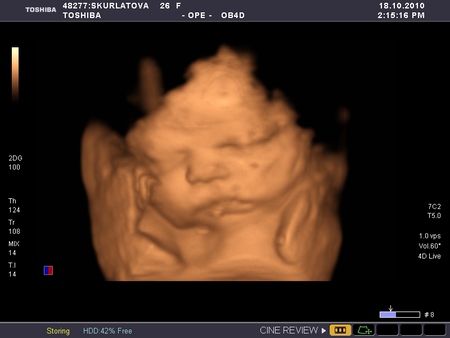

Вчера были на УЗИ, видели нашего мальчугана! Такой смешнючий, щечки отъел серьезные! Весим 2200, лежим правильно головкой вниз, регулярно маме левый бок разминаем, икота - сказали не страшна, просто водички перепил. Однократное обвитие пуповиной вокруг шейки, не тугое, врач сказала, что еще может скинет эту петельку, а в остальном все в полном порядке!

Фотки прилагаются:

Спасибо))) Да, самое главное здоровье!!! А личико мы тоже еле поймали, он пальцы грыз и ручками закрывался)))